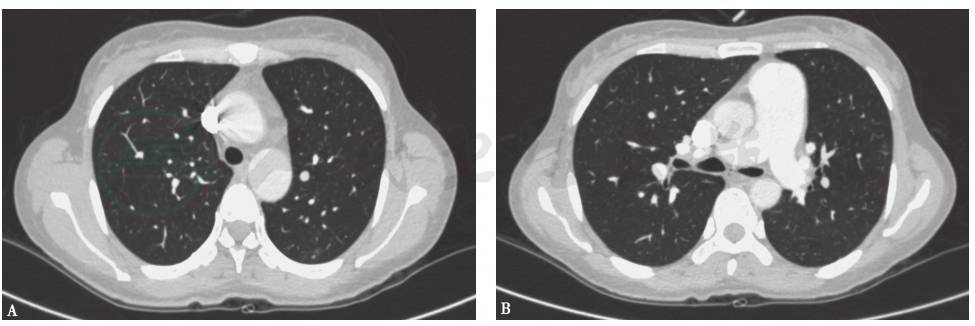

胸部CT(2014年10月16日):双肺散在小结节影,未见结节空洞改变、肺门和纵隔淋巴结肿大和胸腔积液征象(图1)。

图1 胸部CT表现(2014-10-16)

胸部CT(2014年12月23日):双肺散在结节影,边界模糊,右肺上叶见薄壁空洞影,未见肺门和纵隔淋巴结肿大,未见双侧胸膜积液(图2)。

图2 胸部CT表现(2014-12-23)